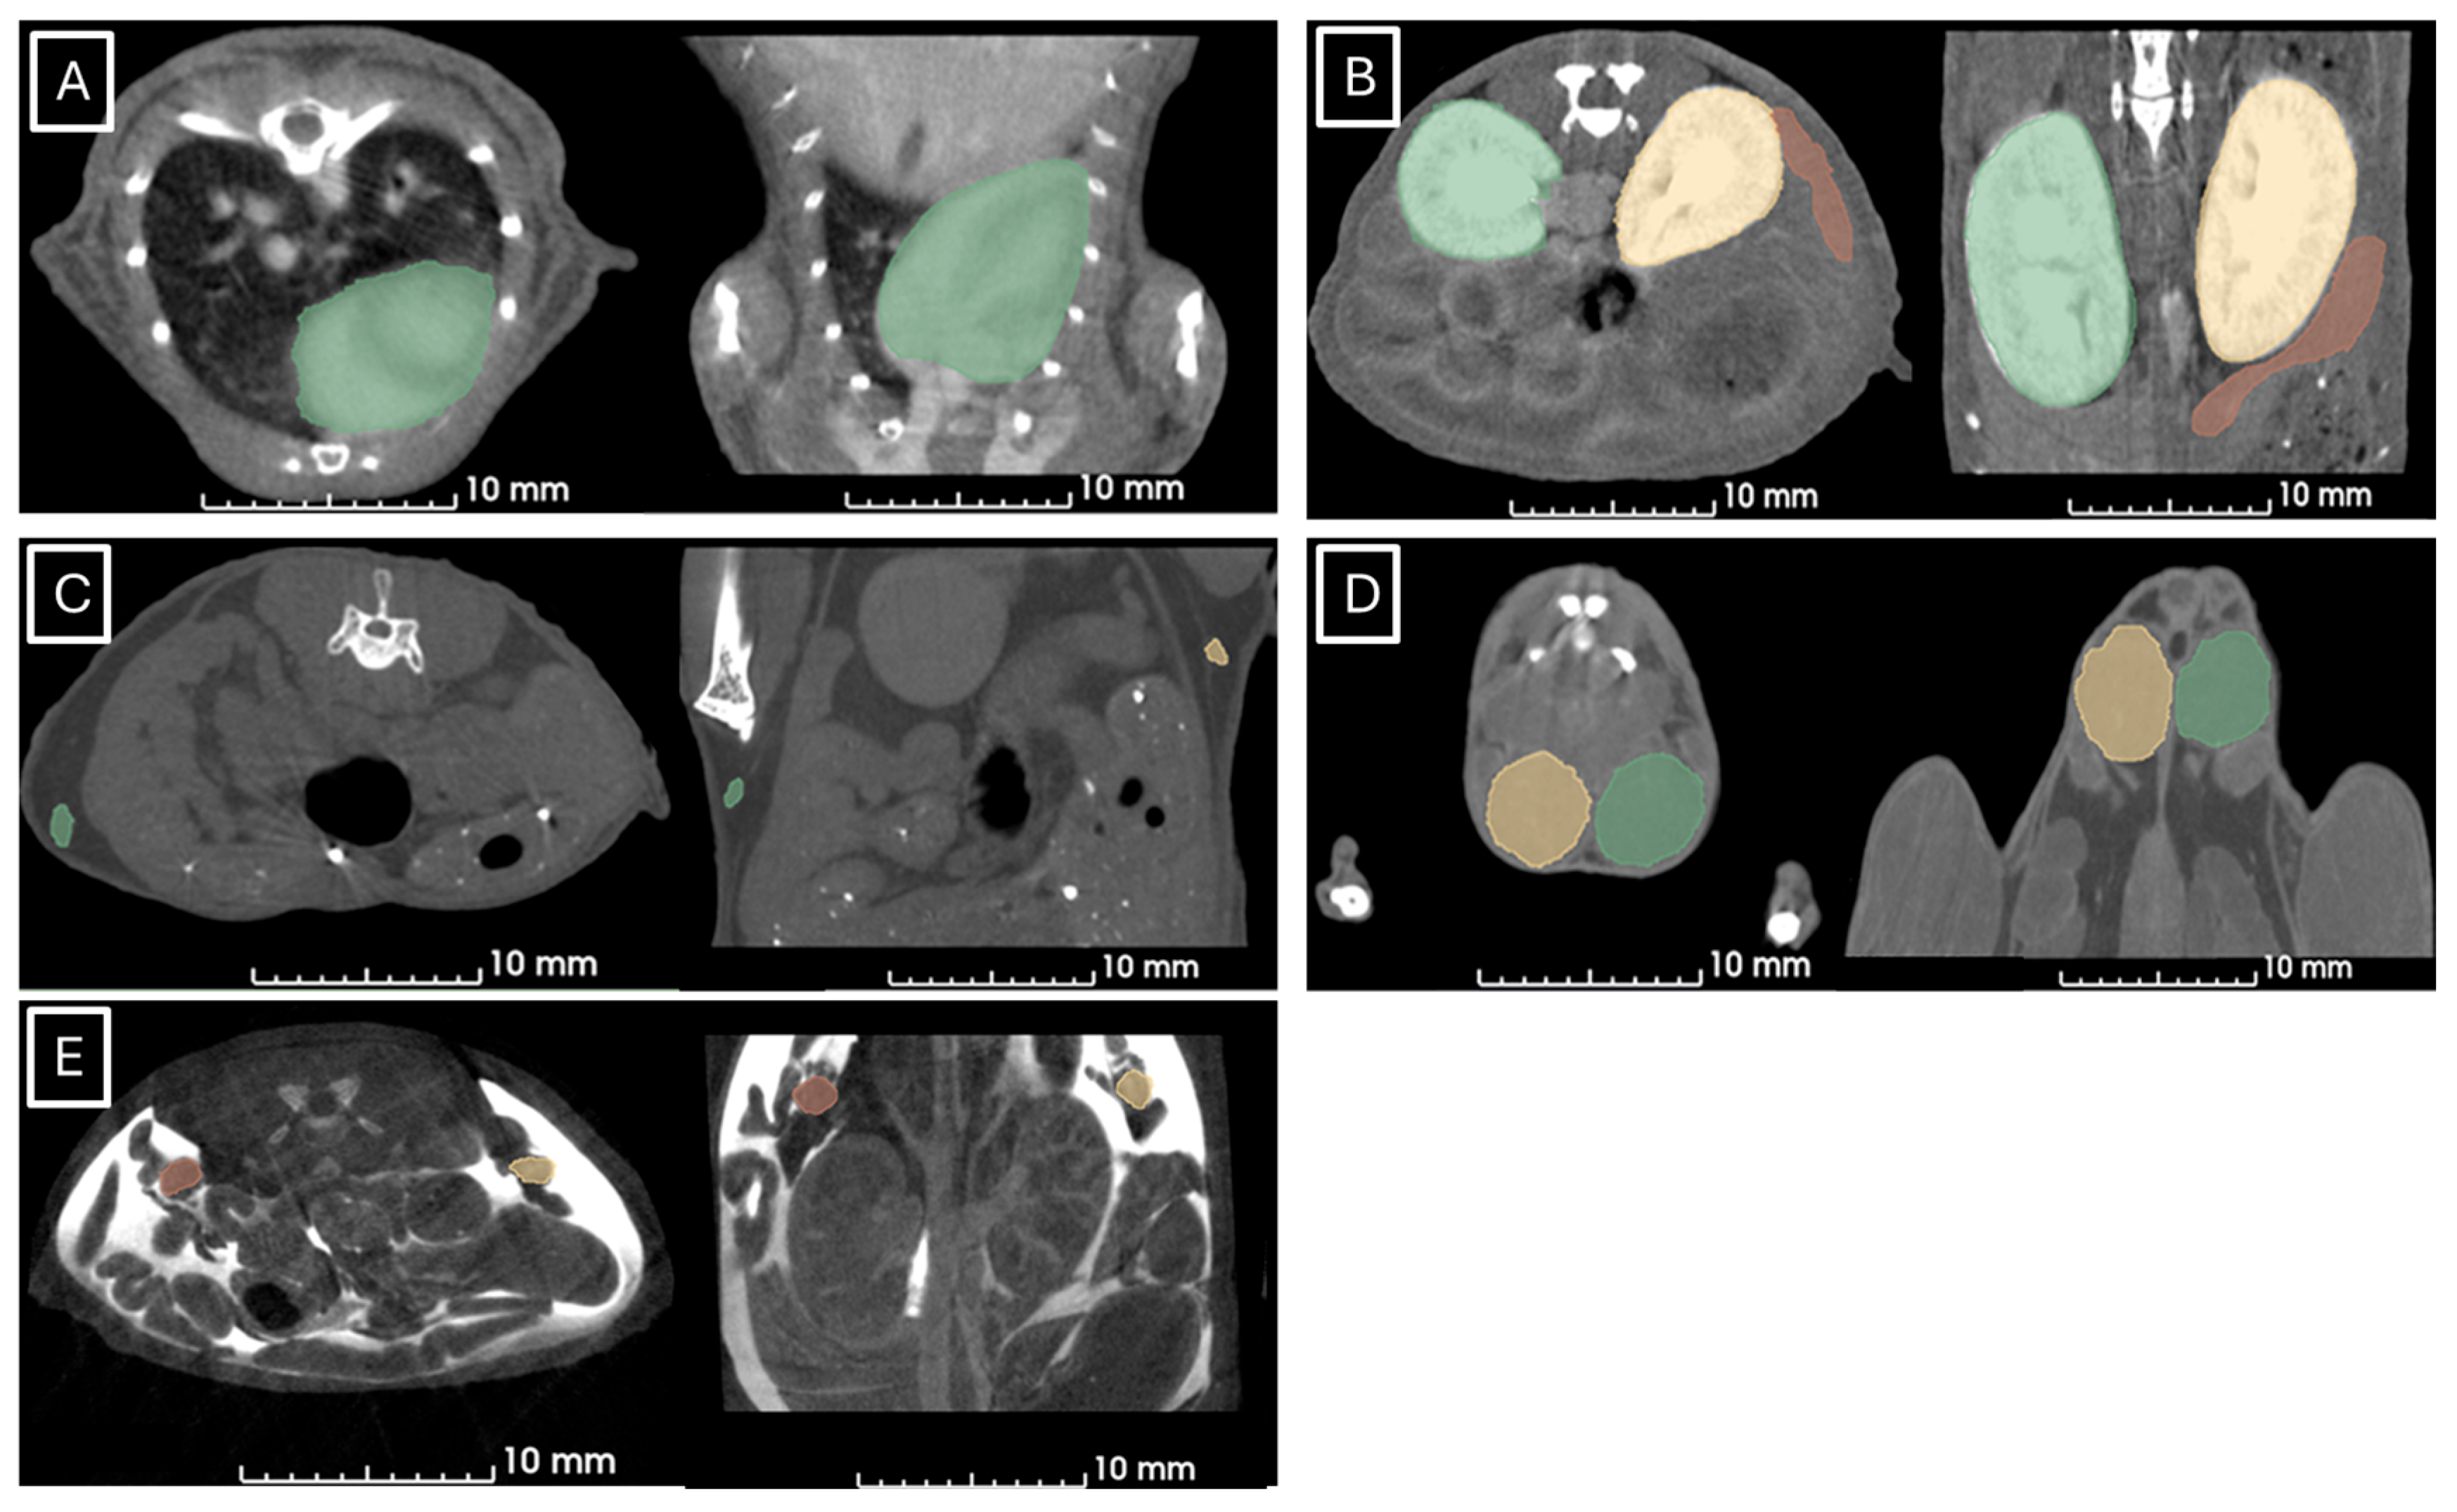

Figure 1 and Figure 2 show examples of ultrasound and microCT diameter measurements. Figure 3 shows examples of manual segmentation.

Figure 3.

Representative images of manual segmentation in microCT studies. (A) Segmented heart in green in axial (left) and coronal (right) views, (B) left kidney in yellow, right kidney in green, and spleen in red segmented in axial (left) and coronal (right) views, (C) left (in green) and right (in yellow) lymph nodes in axial (left) and coronal (right) views, (D) left (yellow) and right (green) testicles in axial (left) and coronal (right) views, (E) left (orange) and right (yellow) ovaries in axial (left) and coronal (right) views.